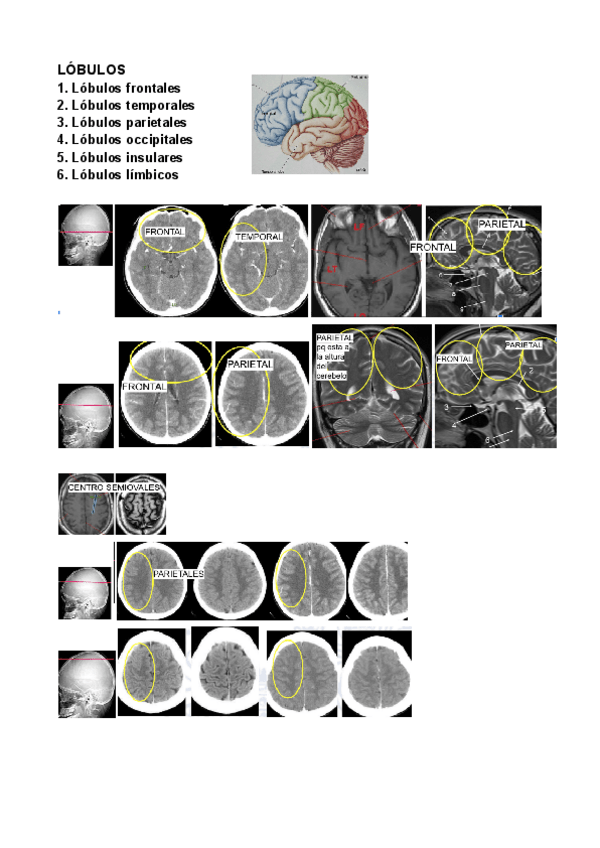

tema-1-snc.pdf